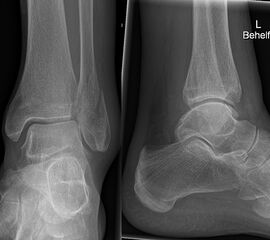

Die Standard-Röntgenaufnahmen des oberen Sprunggelenks bestehen aus drei Aufnahmen: der antero-posterioren Aufnahme (ap), der antero-posterioren Aufnahme mit Innenrotation des Unterschenkels von 20° („Mortise view“), sowie der streng seitlichen Aufnahme (siehe S2-Leitlinie Sprunggelenksfraktur). In der Röntgen-Bildgebung sollte neben den klassischen Frakturzeichen die Integrität der Syndesmose beurteilt werden. Dies erfolgt über die Beurteilung der Breite des lateralen und medialen Gelenkspalts („medial clear space“), des tibiofibularen Abstands 1cm oberhalb des OSG-Gelenkspalts („tibiofibular clear space“), bzw. der tibiofibularen Überlappung. Eine Verbreiterung des tibiofibularen Abstands über 5 mm oder die Erweiterung des medialen Gelenkspalts können Zeichen einer begleitenden Syndesmosenverletzung sein. (Abbildung 3) 6.

Liegt eine Fraktur des oberen Sprunggelenks vor, ist sowohl zur Entscheidung für ein konservatives oder operatives Vorgehen, als auch zur Operationsplanung, ein ausreichendes Verständnis der Fraktur und ihrer Morphologie notwendig. Insbesondere bei komplexen Verletzungen ist dafür die konventionelle Röntgenaufnahme in vielen Fällen nicht ausreichend. So konnten z.B. Black et al. zeigen, dass die operative Strategie zur Versorgung von OSG-Frakturen in 24% basierend auf einer zusätzlichen CT-Bildgebung relevant geändert wurden 7. Dies betraf die Lagerung, die Wahl des Zuganges und die Art der osteosynthetischen Versorgung. Besonders häufig änderte sich das Vorgehen bei Verletzungen des medialen (21%) und des posterioren Malleolus (15%). Darüber hinaus führten dislozierte (dislozierte Frakturen 31% vs. nicht-dislozierte Frakturen 20%) oder komplexe Frakturen (Trimalleolar-Frakturen 29% vs. Unimalleolar-Frakturen 10%) besonders häufig zu relevanten Änderungen des operativen Vorgehens. Die Computertomographie ist daher, insbesondere bei Bi- und Trimalleolar-Frakturen, essentiell für das Verständnis der Fraktur und somit für die Planung und Durchführung der Operation. In Abbildung 4 und 5 sind exemplarisch ein Röntgen- und ein CT Befund gegenübergestellt.

Luxationsfrakturen (Abbildung 7) sollten unter i.v.-Analgesie so schnell wie möglich reponiert werden, um Haut- und Weichteilschäden, Störungen der Durchblutung und Sensibilität, sowie den durch die Fehlstellung bedingten Druck auf den Knorpel zu verringern. Anschließend erfolgt die Ruhigstellung in einem gespaltenen Unterschenkelgips. Offene Frakturen, geschlossene Frakturen mit kritischen Weichteilverhältnissen, sowie hochgradig instabile Frakturen, die sich unter entsprechender Analgesie nicht zufriedenstellend reponieren bzw. retinieren lassen, stellen eine Notfallindikation dar. In diesen Fällen sollte die Anlage eines Fixateur externe erfolgen (Abbildung 8). Die definitive Frakturversorgung erfolgt zweizeitig nach entsprechender Konsolidierung der Weichteile. Eine Kompartment-Spaltung ist bei OSG-Frakturen nur sehr selten erforderlich.